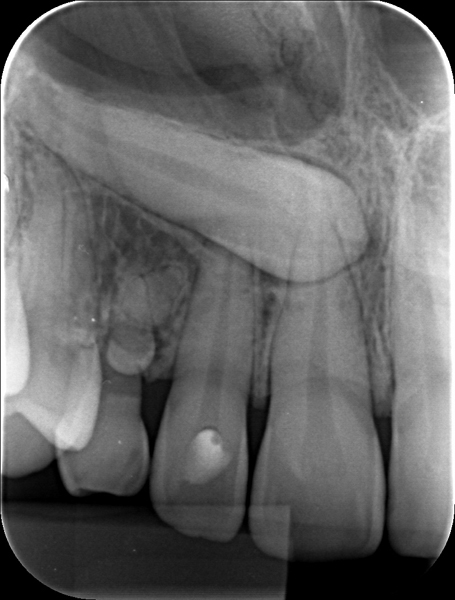

Radiografia Periapical

Radiografia Interproximal

O objetivo principal desta técnica é o exame das faces proximais dos dentes posteriores e da crista óssea alveolar. É indicado na detecção de processos cariosos, adaptações marginais de restaurações e presença de lesões periodontais, que apresentem comprometimento de estruturas ósseas, com destruição da crista óssea alveolar.